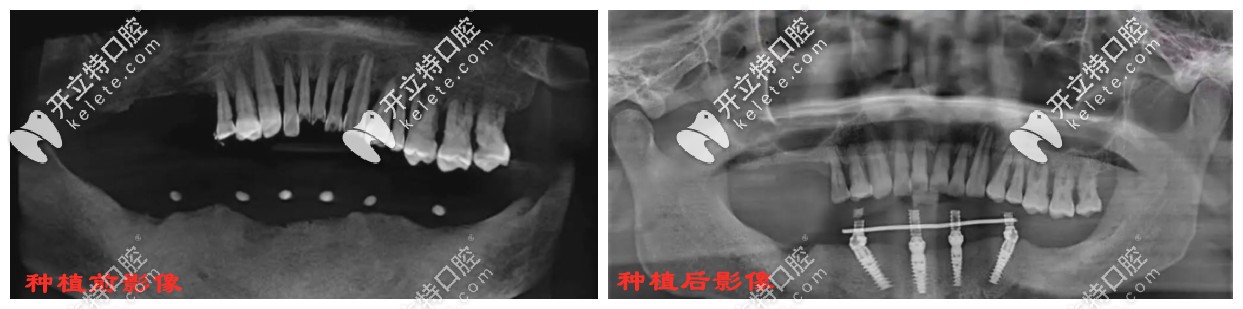

雅度口腔一顧客種植all-on-4前后影像對(duì)比▼

種植牙前后影像對(duì)比